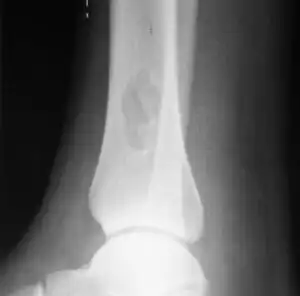

X-ray of nonossifying fibroma of distal tibia.

Diagnosis is by X-ray or MRI, usually when investigating a person for something else.[3] Medical imaging typically shows a well marginated radiolucent lesion, with a distinct multilocular appearance, sometimes looking like bubbles.[3] It is usually around 1-2cm in size, but be as large as 7cm.[4] They consist of foci consist of collagen rich connective tissue, fibroblasts, histiocytes and osteoclasts.[3] Usually no treatment is required.[4] Surgical curettage and bone grafting may be required if it is large.[4]

It is usually iagnosed by x-ray or MRI, when investigating another problem.[1] The tumor presents as a well defined radiolucent lesion, with a distinct multilocular appearance, sometimes looking like a "soap bubble".[2] If small and no symptoms, then biopsy is not needed.[1]